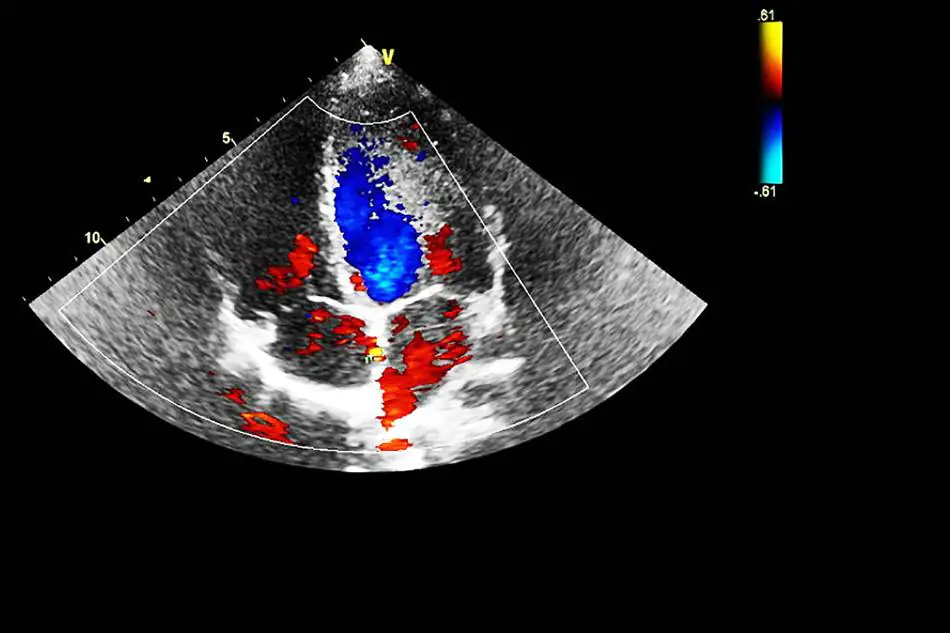

L’ecocolordoppler (correntemente definito ECODOPPLER) è un metodo diagnostico non invasivo, che consente di visualizzare l’ecografia dei vasi sanguigni e si occupa di studiare i flussi ematici al loro interno.

È un procedimento più evoluto rispetto all’ecografia Doppler: è in grado di corredare informazioni ancora più dettagliate rispetto al flusso ematico dei vasi sanguigni e associa in tempo reale un’immagine ecografica bidimensionale a un segnale pulsato di tipo Doppler.